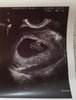

Hejka melduję po USG ciąża starsza o 3dni, czyli mam 8tydzien i 3dni. Serce bije 176 uderzeń na minutę. Jest jedno ale mam torbiel niewielką ale w pochwie zaraz za cewką, trzeba obserwować ale nie zagraża ciąży bo jak powiedział lekarz jest na zewnątrz. I tyle 9 listopada mam przyjść z badaniami zrobionymi.